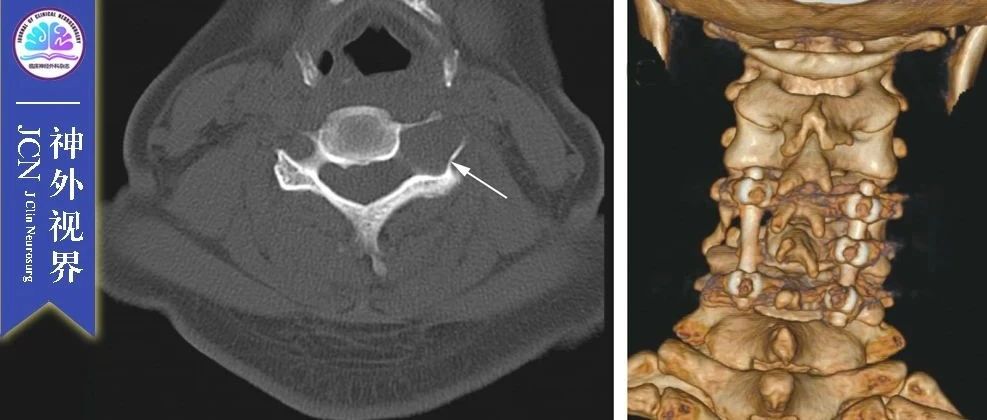

晏怡,重庆医科大学附属第一医院神经外科神经脊柱专业组组长,主任医师,教授,医学博士,硕士研究生导师,国内知名脊髓脊柱神经外科专家。担任中华医学会神经外科分会脊柱脊髓学组委员,中国医师协会神经外科医师分会脊柱脊髓专家委员会委员,重庆市医学会神经外科专业委员会脊柱学组组长。1994年毕业于华西医科大学医学系,2006年获医学博士学位。擅长领域:脊髓脊柱疾病、脊髓肿瘤、颅颈畸形、椎间盘突出、椎管狭窄、椎体滑脱、脊柱外伤、脊柱侧弯、脊髓栓系等;在各种脊髓肿瘤、颅颈畸形、椎间盘突出、脑肿瘤的显微外科手术方面经验丰富。近年来发表论文50余篇,其中SCI论文5篇,参编专著部,主持重庆市自然科学基金课题1项,重庆卫生局科研基金资助课题1项,参与卫生局课题2项。...